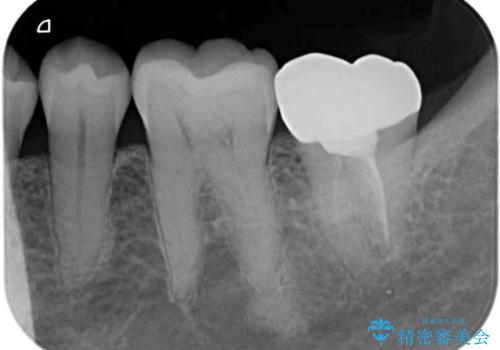

- 神経が取り除かれた歯が欠けてしまったとのことで来院された患者様です。

破折線が歯肉の中、深いところにまで及んでいる場合には歯周外科の適用となることを伝えた上で、補綴治療を行うこととしました。

破折部位を除去したところ、外科処置が必要な深さまで破折線が及んでいなかったため、速やかにジルコニアクラウンにて補綴を行うことになりました。

神経が取り除かれた歯、特に奥歯では、歯の破折が起こりやすいので、クラウンによる補綴治療が必要であることを実感した治療でした。